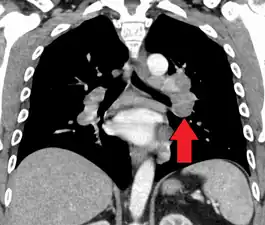

Hilar adenopathy especially on the person's left (coronal CT)